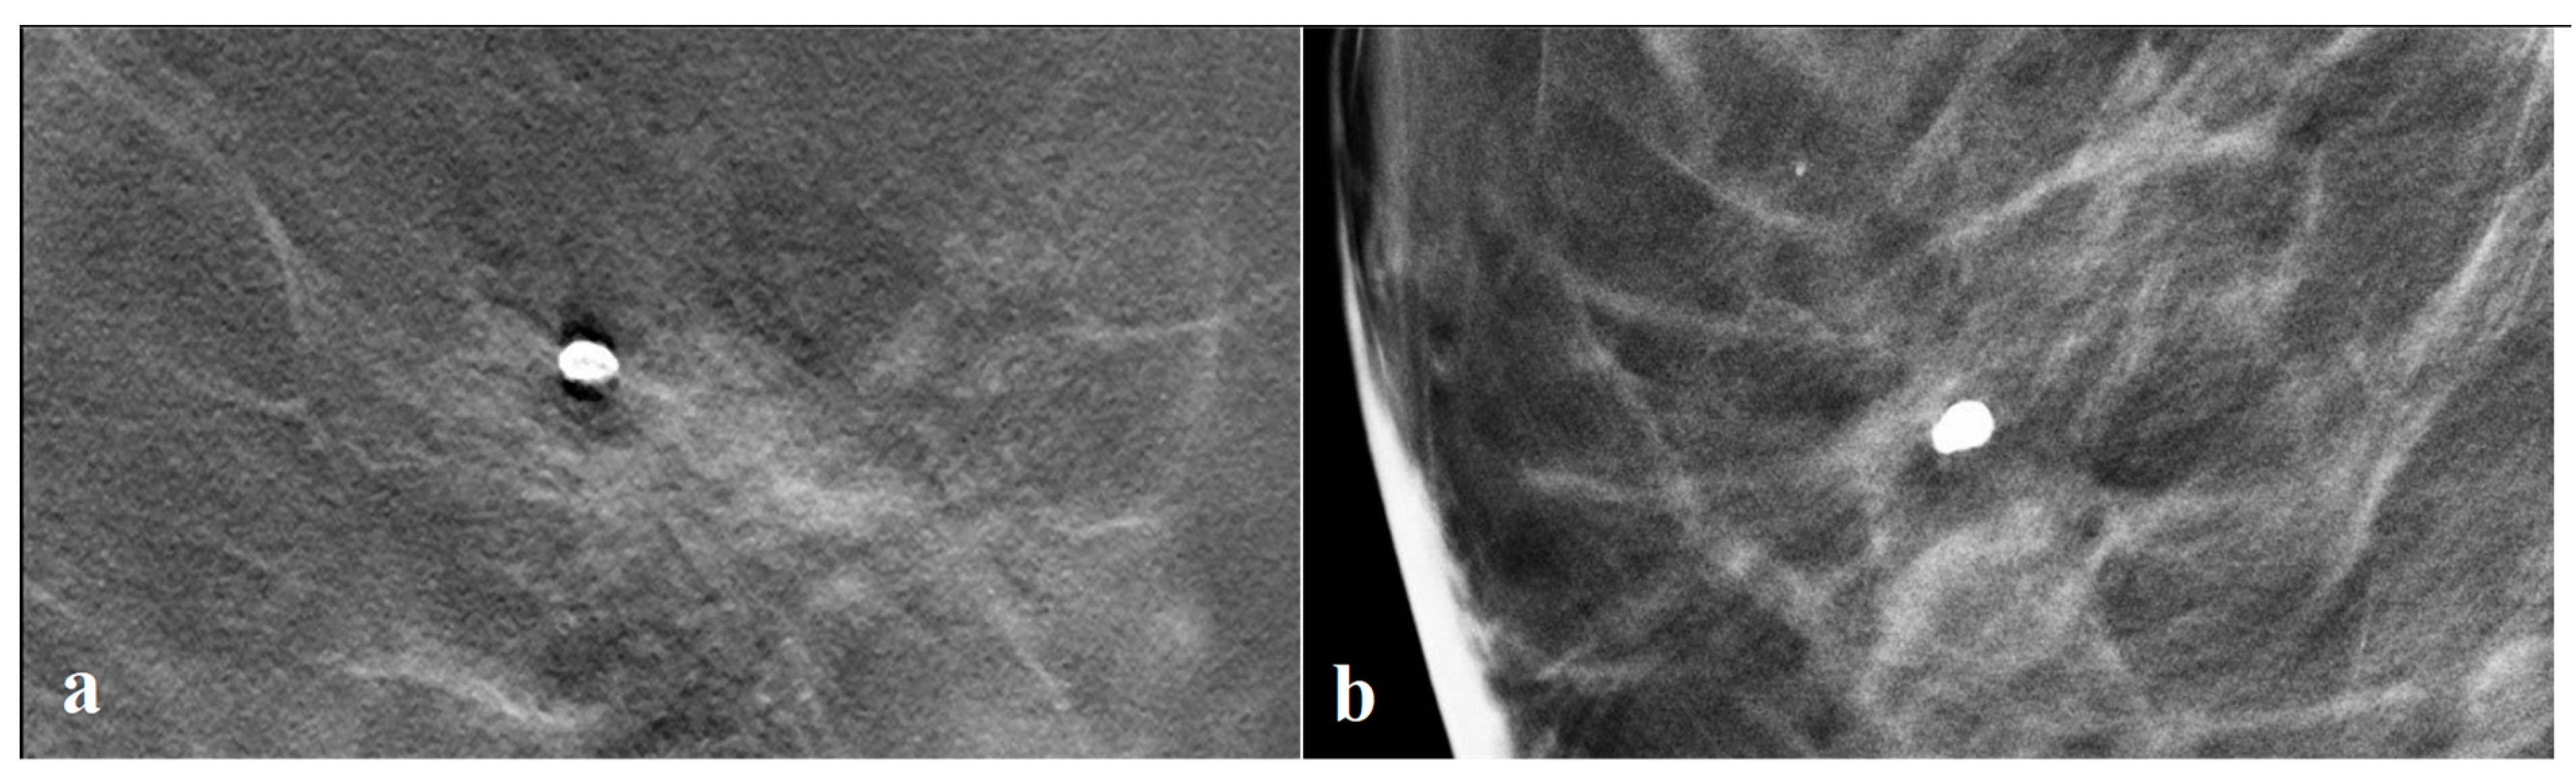

3.3. Tomosynthesis Evaluation